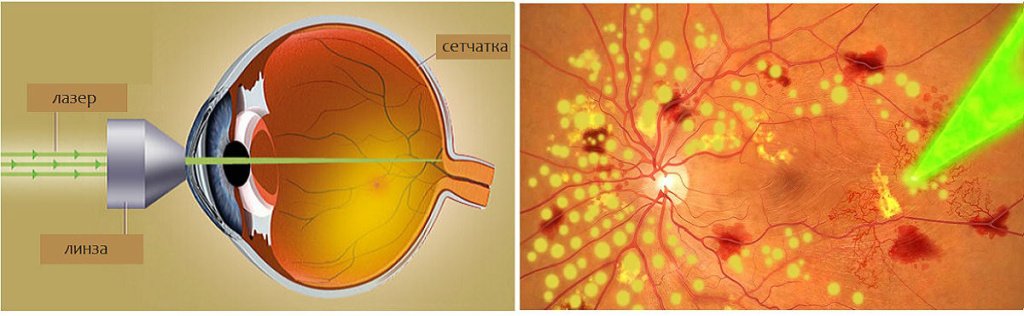

Изображения и анатомия сетчатки глаза

Раздел: Визуальный дайджест